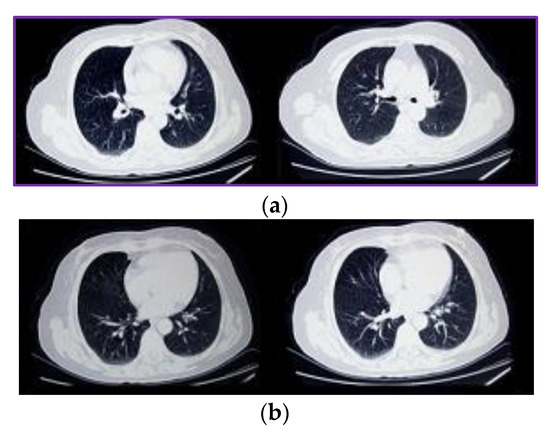

The proposed model for COPD analysis uses an ensemble of VGGNet, AlexNet, ResNet18, and GoogLeNet CNN models. These models are selected based on the advantages and shortcomings in each of them. The VGGNet model is capable of high accuracy coarse classification, wherein images of different visual appearance can be classified with accuracies in the range of 95 to 98%. However, for minor changes in the images, the accuracy of VGGNet model reduces drastically. For instance, if lung nodule locations are widely separated as shown in Figure 5a, then VGGNet model works perfectly, but if the lung nodule locations for different disease types change infinitesimally as shown in Figure 5b, then the accuracy of the VGGNet model is not guaranteed.

Figure 5.

(a) Lung nodule positions for COPD (right) and non-COPD images. (b) Small changes in lung nodule positions for COPD and non-COPD images.